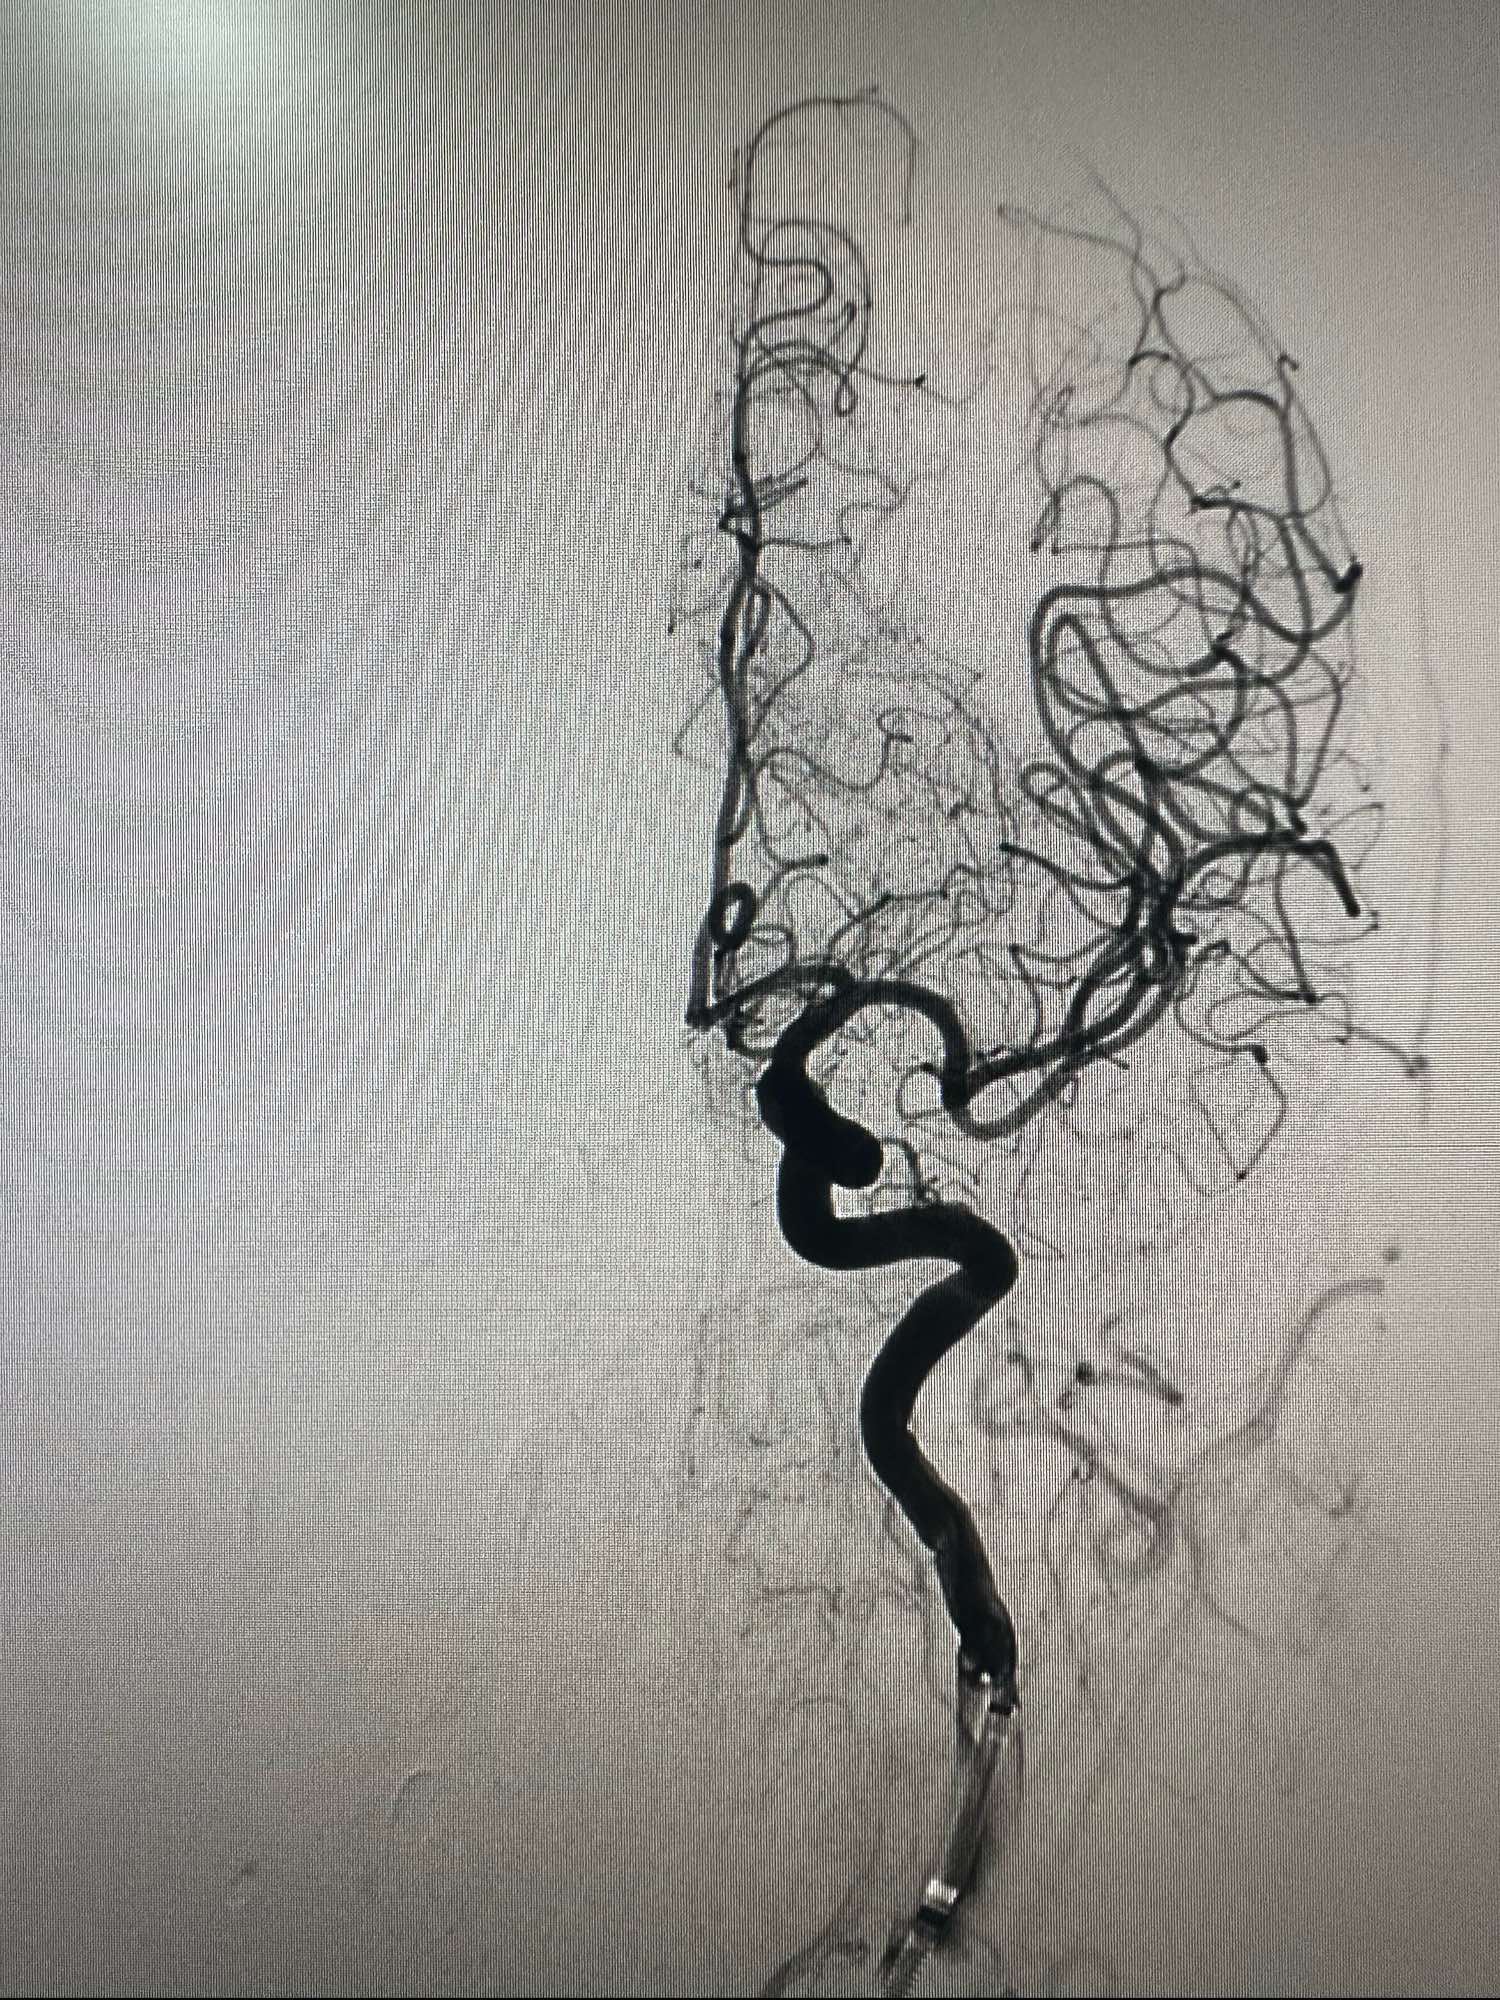

右侧颈内动脉造影正位